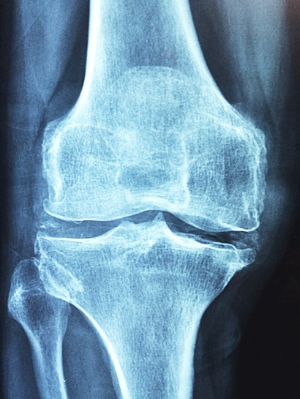

5. 수술: 관절염이 심각한 경우, 관절 대체 수술이나 관절 수술을 고려할 수 있습니다. 이는 환자의 증상을 개선하고 관절의 기능을 회복하는 데 도움이 됩니다.

류마티스 관절염은 초기에 발견하고 적절한 치료를 시작하면 완치 가능성이 높아집니다. 초기 증상이 발견되면 가까운 정형외과 또는 재활의학과를 방문하여 정확한 진단과 치료를 시작해야 합니다. 이 질병은 빠른 시기에 치료하지 않으면 심각한 손상을 일으킬 수 있으므로 주의가 필요합니다.